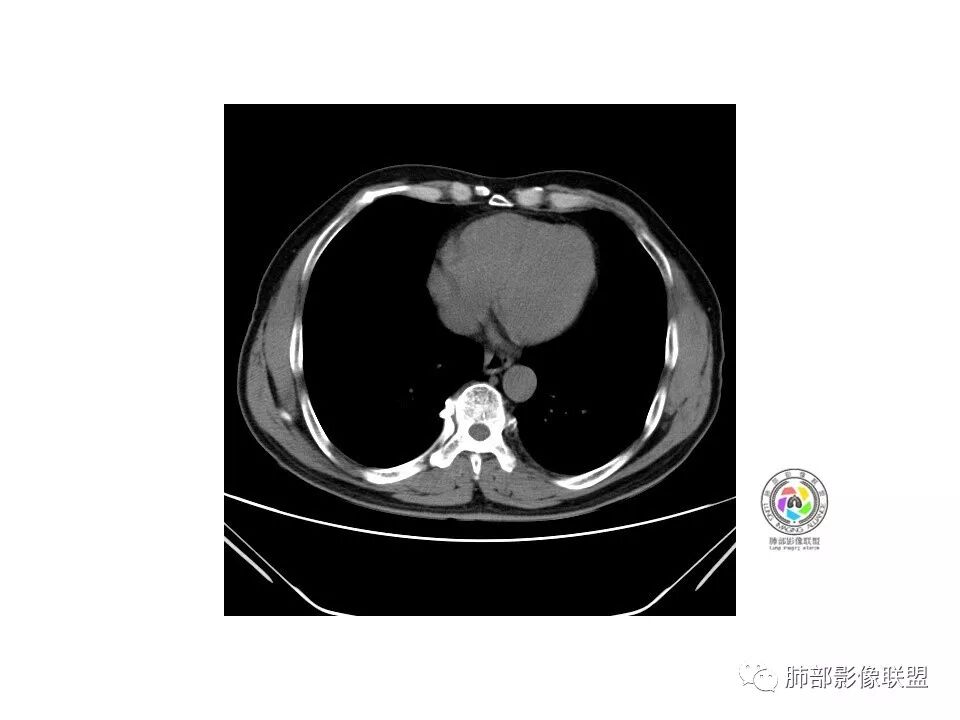

右肺下叶见边界清晰混合磨玻璃密度影,目测内见实性结节小于5mm,有浅分叶,前缘小叶间隔阻挡,月牙铲?胸膜牵拉,老年患者,MIA可能,鉴别炎性病变,抗炎后复查

患者老年男性,以咳嗽 、咳痰3天就诊,胸CT:右肺下叶前基底段mGGO,内可见血管形态改变,细支气管扩张,病灶边界清,边缘可见月牙铲。考虑恶性,腺癌?但建议先抗炎治疗后复查

患者老年男性,咳嗽  咳痰3天就诊。胸部CT:右肺下叶前基底段混合磨玻璃结节,边缘清楚,可见毛刺、胸膜牵拉、血管集束、月牙铲征象。综合考虑微浸润腺癌可能大。

右肺下叶前基底段混合磨玻璃结节,边界清,浅分叶,胸膜牵拉,月牙铲,血管进入,考虑:微浸润腺癌可能性大,抗炎后复查。

老年男性,咳嗽、咳痰3天。胸部CT:右肺下叶前基底段mGGN,边缘清楚,内可见不规则实性成分,病灶可见空泡、毛刺、胸膜牵拉、血管集束征象。考虑MIA可能大,抗炎2W后复查。

老年男性,右下肺前基底段混合GGN,边缘清晰,月牙铲,叶间胸膜牵拉,有轻度收缩力。结合病史抗炎2-3周后复查,消失考虑炎症,变化不大为腺癌。本例总体支持腺癌

老年男性,咳嗽3天,右肺下叶前基底段混合磨玻璃结节,形态不规整,相邻胸膜凹陷,可见血管影,考虑腺癌可能性大,不除外炎症可能,建议抗炎1~2周,1个月复查胸部CT。

老年男性,右肺下叶前基底段斜裂旁可见单个混合型磨玻璃结节mGGN,边缘清,内部结构紊乱,进入的血管增粗,支气管关系不好判断,斜裂侧可见牵拉,常规考虑微侵腺癌MIA,建议先抗炎后复查及手术干预。

老年男性,咳嗽咳痰3天。MGGN,边缘见月牙铲、胸膜牵拉,血管移动联通?冠状位隐约可见支气管穿行,考虑MIA,重建冠位可见结节比较靠近叶裂,可积极手术处理。

老年男性,右S8混合磨玻璃结节,边缘尚清晰,局部凹陷,叶间胸膜牵拉,考虑MIA可能大,建议抗炎治疗10天,6-8周后复查

患者老年男性,右下肺前基底段靠近胸膜侧可见一个mGGO结节,边缘清淅,可见分叶征及月牙铲,小结节病灶胸膜牵拉明显,首先考虑MIA可能性大。

右肺下叶前基底段mGGN,边界清晰,内部结构杂乱,见网格空泡感,月牙铲,浅分叶及胸膜牵拉,倾向MIA。